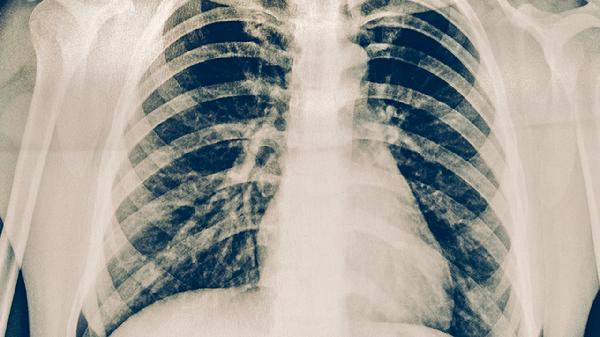

肺癌放疗后可在医生指导下使用吉非替尼片、盐酸厄洛替尼片、注射用培美曲塞二钠、卡铂注射液、复方斑蝥胶囊等药物。放疗后用药需根据患者病理类型、基因检测结果及不良反应个体化选择,药物主要用于控制肿瘤进展、缓解放疗副作用或调节免疫功能。

盐酸厄洛替尼片同样针对EGFR突变阳性肺癌,能阻断肿瘤信号传导通路。放疗后使用可延缓局部复发,但可能加重间质性肺病风险。服药期间应避免强效CYP3A4诱导剂,并定期进行胸部影像学检查。

肺癌放疗后患者应保持高蛋白、高维生素饮食,适量补充瘦肉、鸡蛋、西蓝花等食物。避免辛辣刺激性食物,少食多餐缓解消化道反应。适当进行呼吸功能锻炼,如腹式呼吸、缩唇呼吸等。定期复查血常规、肝肾功能及胸部CT,出现持续咳嗽、胸痛加重或不明原因发热时及时就诊。严格遵医嘱用药,不得自行调整剂量或停药。